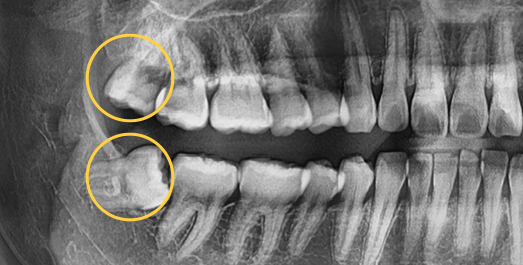

Some wisdom teeth erupt normally, but others may erupt at an angle, horizontally, or remain fully impacted. Wisdom teeth that do not erupt properly can disturb the dental arch and are difficult to clean, which may lead to decay of adjacent molars. In such cases, extraction is recommended.

• Horizontally

impacted wisdom tooth

• Angulated

• Vertically